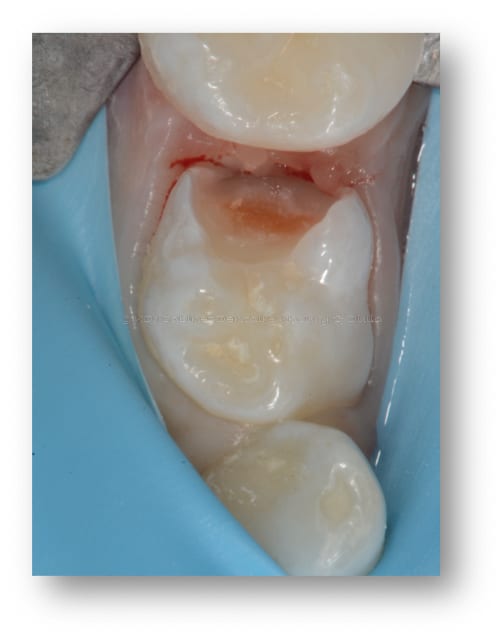

Les différentes étapes pour soigner une carie sur une molaire de lait sont illustrées, depuis l’ouverture de la cavité carieuse, le nettoyage du tissu malade et la restauration de la dent avec du composite.

Caries dentaires affectant deux molaires de lait